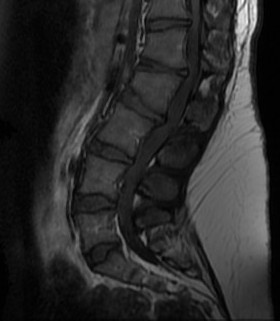

Spinal canal stenosis

- decreased inter-pedicular distance

- narrows from L1 down (normally increases)

- short pedicles

Platyspondyly

- bullet shape vertebrae

- anterior inferior body beak T12- L2

- posterior scalloping of vertebral bodies

Spinal Stenosis

Present later in life

- 50% or more of patients

- require multilevel laminectomy +/- fusion